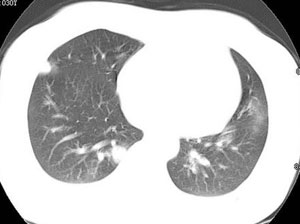

女性,30岁。

病史为胸痛20多天,无畏寒发热,无消瘦,无咳嗽咳痰。总之症状很逍遥。

临床以胸痛待查收住入院。

双肺野可见散在大小不等结节及肿块影,内密度不均匀,边缘部分清,部分欠清,纵隔未见明显肿大淋巴结.右侧胸腔少理积液.结合临床,考虑韦格肉芽肿可能吧,巨淋巴增生,结节病,特殊感染都要考虑.转移瘤临床不象.

多发、内可见含气支气管征,边界不清;纵隔内未内见明显肿大淋巴结。右侧少量胸腔积液。

考虑:1、化脓性肺炎?

2、肺霉菌感染?

本病例特点如下:

1.青年女性,以胸痛20多天就诊,无呼吸道及感染临床症状体征,无原发肿瘤病史;

2.肺ct表现为两肺多发大小不等结节影,大结节位于肺尖部,小结节多位于肺外带胸膜下,大结节内可见支气管充气征,周围可见月晕征(指在结节状或肉芽肿样病灶周围呈环形磨玻璃影),右肺门及腔静脉后可见小淋巴结,右侧胸腔内少量液体。

两肺散在分布大小不等的肿块及结节影,边缘毛糙,有分叶、毛刺,病灶密度不均匀,可见支气管充气相与空泡征。病变大多位于胸膜下,可见胸膜凹陷及胸腔积液。气管腔静脉间可见小结节影。